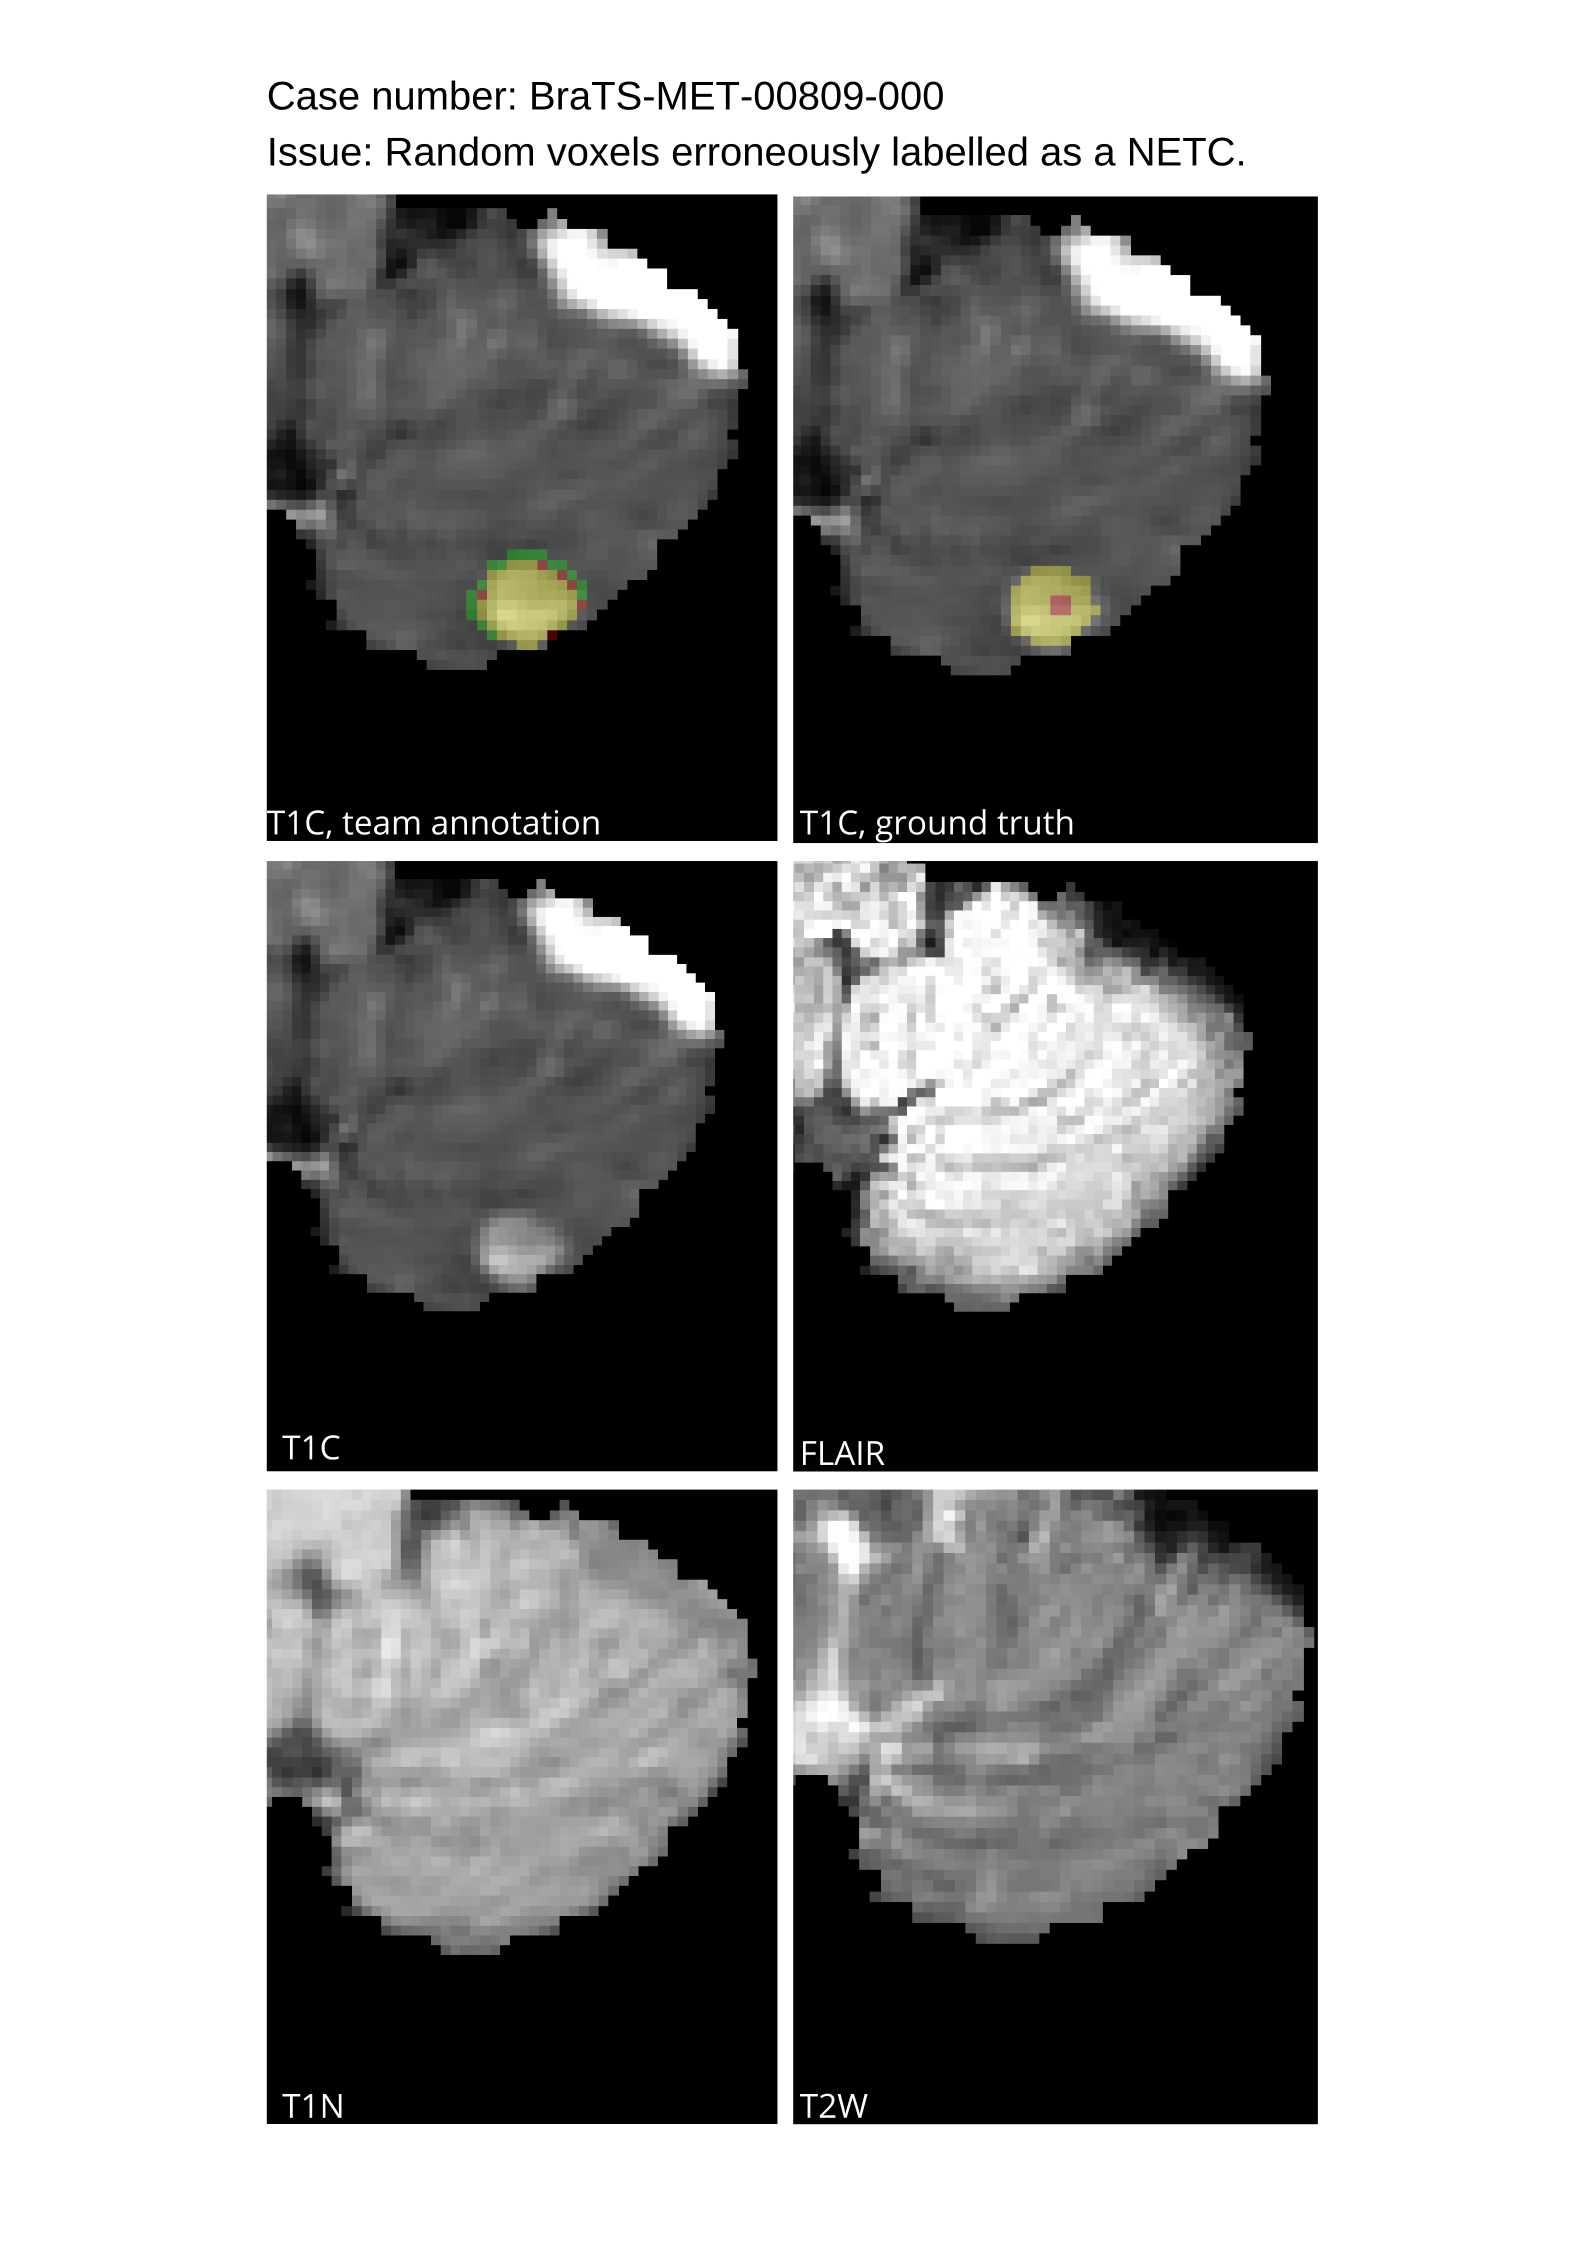

Approvers reviewed the volunteer annotations and either approved the case or returned it to students for re-annotation. Additionally, a QC process was implemented, which included removing all random voxels and any voxels outside the brain mask, ensuring all images had the same parameters (space, orientation, and origin) as the SRI24 atlas, and verifying the presence of all segmentations and segmentation masks are in the folder with original NIfTI images.

4.9 Common Errors of Automated Segmentations

Based on observations from previous BraTS challenges, common errors in automated segmentations were identified. The most typical errors in the current challenge included:

2. 2.

Segmentation of white matter changes from microvascular disease. Peritumoral edema segmentations were checked by neuroradiology attendings and modified.